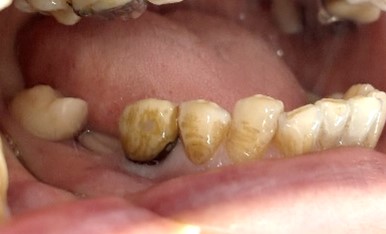

男性Kさん 50代(インプラント)

主訴

歯がグラグラするところ、むし歯のところ、しみるところ、被せ物がとれたところ、歯茎が腫れて血が出るところ、歯が抜けているところがある。すべて治したい。

治療内容

残っている歯を抜歯し、上下インプラント治療をしました。

所感

歯周病が進行している歯、むし歯が進行している歯がほとんどで、レントゲンを撮り、詳しく診てみると、ほとんどの歯を保存することができないことがわかりました。抜歯後は、入れ歯かインプラントの方法があります。治療開始前に患者さんに詳しく現状を説明し、治療法についてじっくり相談しました。自分の歯と同じような感覚で食事できるインプラント治療を選択されました。治療後、表情がとても明るくなり、口元がとても自然で10歳以上若返ったように感じました。「時間はかかりましたが、インプラントにして本当に良かったです!」と素晴らしい笑顔でお話ししてくださいました。